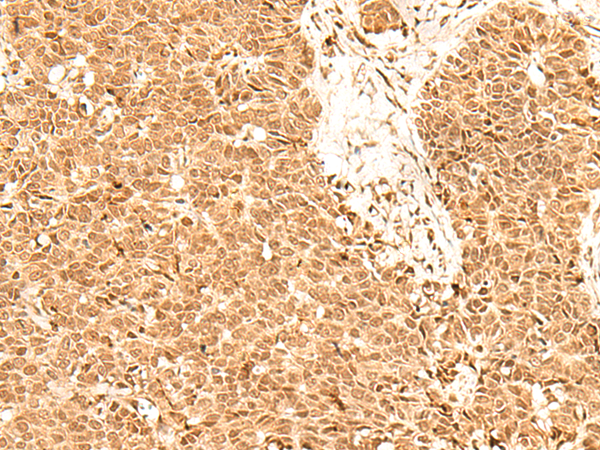

分类: 科研抗体货号: P09924别名: PD2; F23149_1应用: IHC反应种属: Human, Mouse, Rat